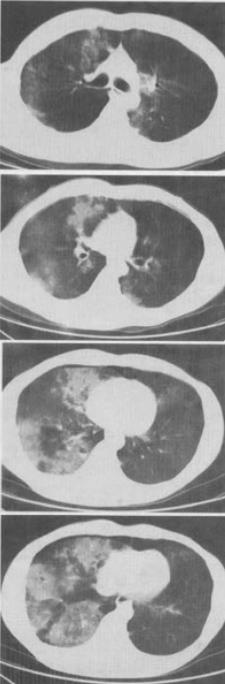

男,28岁,外伤后1小时,胸部CT如图,最可能的诊断为()。

A、肺炎

B、肺脓肿

C、肺囊肿

D、肺癌

E、双肺挫伤

E